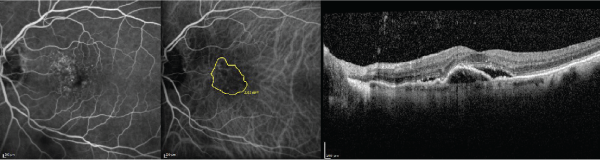

Figure 1: The baseline fluorescein angiography (left), indocyanine green angiography (middle), and optical coherence tomography (right) images are displayed in

a 72 year-old treatment-naïve subject with a Snellen visual acuity of 20/50.

There were 88.2 % (15/17) of subjects that had a reduction in CNV size at the 6-month follow-up evaluation after initiating biweekly bevacizumab. CNV size on ICG angiography enlarged by 33 % or more in 29.4 % (5/17) from treatment naivety until the evaluation in which biweekly bevacizumab therapy was decided upon. CNV size on ICG angiography decreased by 33 % or more in 47.0 % (8/17) at the 6-month follow-up evaluation after initiating biweekly bevacizumab; CNV size on ICG angiography decreased by 33 % or more in 0 % from treatment naivety until the evaluation in which biweekly bevacizumab therapy was decided upon (Figures 1-3).

Figure 2: The fluorescein angiography (left), indocyanine green angiography (middle), and optical coherence tomography (right) images are displayed in the same

subject as Figure 1 after 8 consecutive monthly bevacizumab injections and 4 aflibercept injections. The Snellen visual acuity has decreased to 20/60. Note the

enlargement in choroidal neovascularization surface area from baseline.